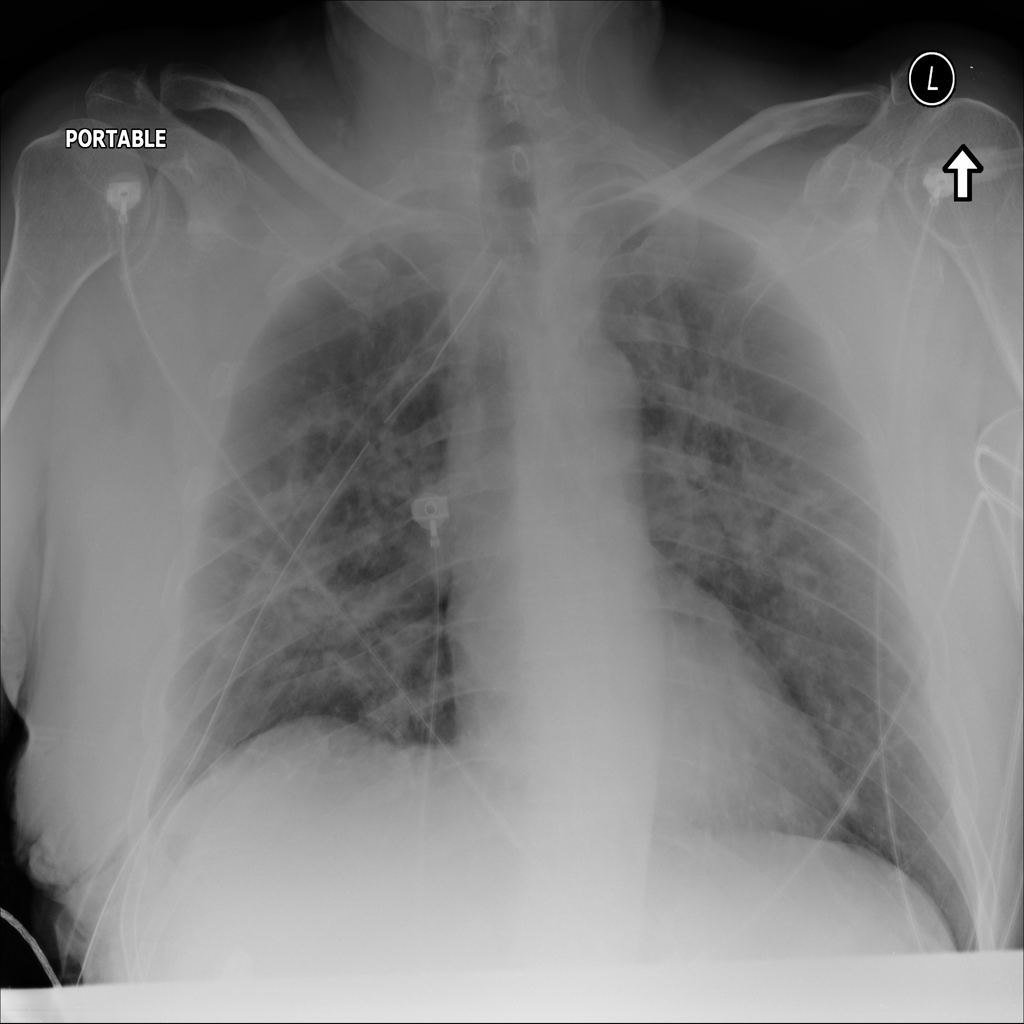

PAT-E828 · IMG-005Edema

PAT-E828 · IMG-005

AP